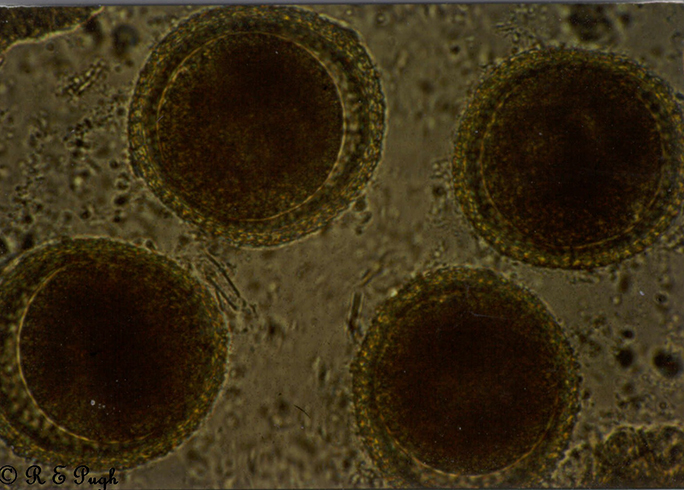

Микрофотографии яиц гельминтов Toxocara canis

Раздел: Фотоэссе